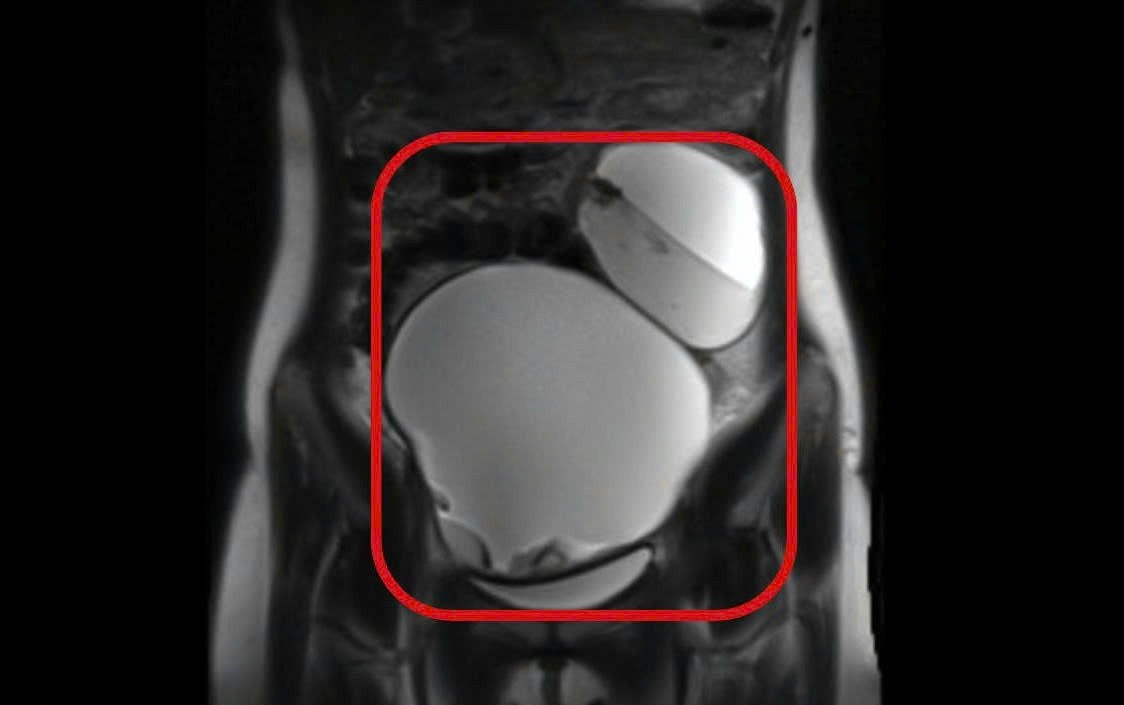

Khối u bì buồng trứng bị xoắn khiến thiếu nữ đau đớn dữ dội

Qua thăm khám, các bác sĩ ghi nhận vùng hạ vị có khối căng lớn, di động và đau rõ. Kết quả chụp MRI cho thấy tử cung không bất thường, nhưng cả hai buồng trứng đều xuất hiện khối u choán chỗ. Đáng lo ngại, cả hai khối u đều bị xoắn – tình trạng cấp cứu sản phụ khoa có nguy cơ gây hoại tử buồng trứng trong thời gian ngắn nếu không can thiệp phẫu thuật kịp thời. Bệnh nhân được chẩn đoán u bì buồng trứng hai bên xoắn và chỉ định mổ khẩn.